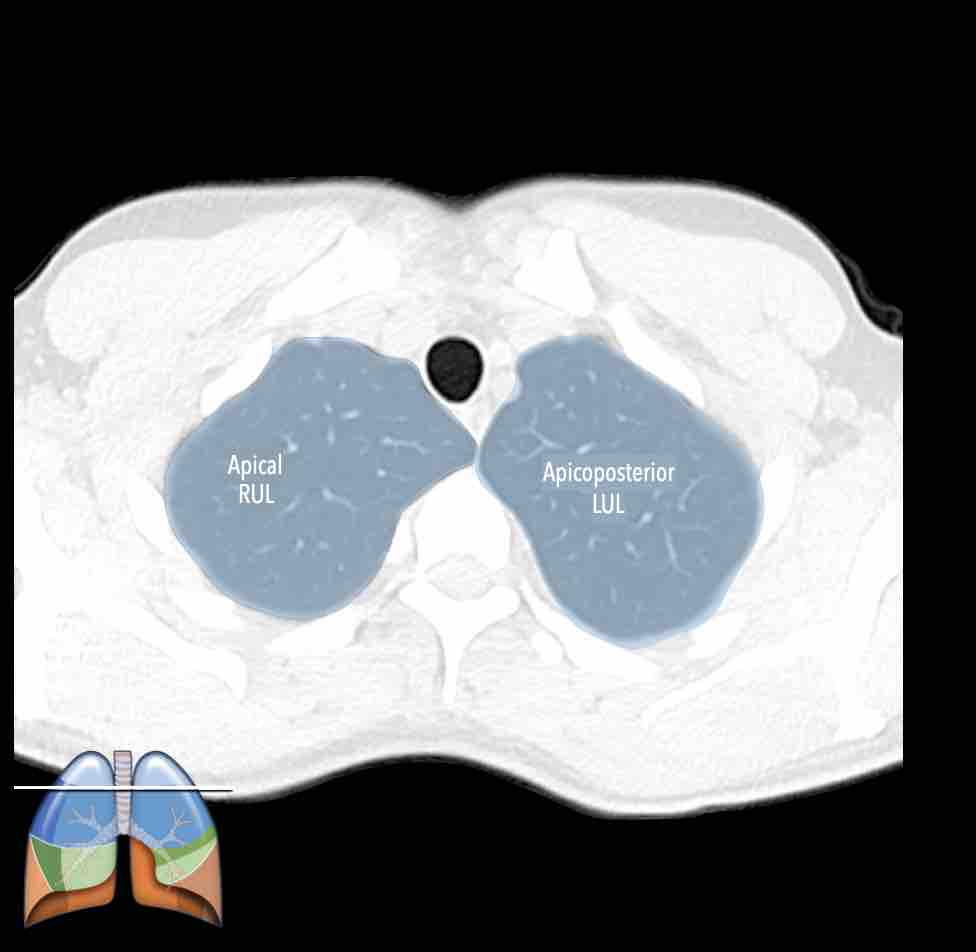

Các phân thùy phổi trên CT

Cuộn qua các hình ảnh để quan sát cách phổi được phân chia thành các phân thùy.